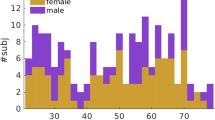

The sample included 84 healthy subjects who are part of the Cuban Project of Human Brain Mapping. This sample was made up of randomly selected subjects of the population of the municipality of La Lisa, Havana. This population is considered representative in terms of ethnic and gender distribution of the Cuban population. Participants were included in the study after reading, accepting and sign an informed consent, in accordance with the ethical standards of the Declaration of Helsinki [14], and the experimental protocols were approved by the Ethics Committee of Cuban Neuroscience Center. A statistical description of the sample is presented in Table 1.

In this paper we assessed if volume, FA and MD values had the same statistical behavior regarding hemisphere and gender using the GLM for rmANOVA, also the age was used as continuous predictor. However, no effect of age was found in the analysis. Subsequently, multiple comparisons were performed across specific contrasts of significant parameters in the model.

Fractional anisotropy

The GLM Repeated Measure ANOVA using FA values (of each tract) as repeated measures, Gender as categorical predictor and Age as continuous predictor (Fig. 2) showed that exist a main effect of FA values (F = 10.489, df = 17, p < 0.001, ɛ = 0.562) and Gender (F = 47.31, df = 1, p < 0.001), with a significant interaction FA values x Gender (F = 4.15, df = 17, p < 0.001, ɛ = 0.569). The data showed bigger values of FA for females than males in all the tracts. By planned comparison analysis were found significant differences for left ATR (F(1,80) = 39.628; p < 0.001) and right ATR (F(1,80) = 33.143, p < 0.001), left CGC (F(1,80) = 38.909; p < 0.001) and right CGC (F(1,80) = 24.015; p < 0.001), left CGH (F(1,80) = 30.044; p < 0.001) and right CGH (F(1,80) = 31.322; p < 0.001), left CST (F(1,80) = 30.110; p < 0.001) and right CST (F(1,80) = 24.472; p < 0.001), Fmj (F(1,80) = 38.574; p < 0.001) and Fmn (F(1,80) = 40.929; p < 0.001), left IFOF (F(1,80) = 44.069; p < 0.001) and right IFOF (F(1,80) = 41.909; p < 0.001), left ILF (F(1,80) = 39.534; p < 0,001) and right ILF (F(1,80) = 34.545; p < 0.001), left SLF (F(1,80) = 45.333; p < 0.001) and right SLF (F(1,80) = 48.343; p < 0,001), left UNC (F(1,80) = 47.514; p < 0.001) and right UNC (F(1,80) = 46.738; p < 0.001) (Fig. 2).

Mean diffusivity

The GLM Repeated Measure ANOVA using MD values (of each tract) as repeated measures, Gender as categorical predictor and Age as continuous predictor (Fig. 3) showed that exist a main showed that exist a main effect of MD values (F = 10.069, df = 17, p < 0.001, ɛ = 0.382) and Gender (F = 55.40, df = 1, p < 0.001) with a significant interaction MD values x Gender (F = 9.000, df = 17, p < 0.001, ɛ = 0.382). The data showed bigger values of MD for males than females in all the tracts.

By planned comparison analysis were found significant differences for left ATR (F(1,80) = 48.650; p <0.001) and right ATR (F(1,80) = 50.375; p < 0.001), left CGC (F(1,80) = 54.193; p < 0.001) and right CGC (F(1,80) = 50.140; p < 0.001), left CGH (F(1,80) = 50.333; p < 0.001) and right CGH (F(1,80) = 43.136; p < 0.001), left CST (F(1,80) = 42.762; p < 0.001) and right CST (F(1,80) = 41.220; p < 0.001), Fmj (F(1,80) = 56.279; p < 0.001) and Fmn (F(1,80) = 57.800; p < 0.001), left IFOF (F(1,80) = 55.654; p < 0.001) and right IFOF (F(1,80) = 56.077; p < 0.001), left ILF (F(1,80) = 51.929; p < 0.001) and right ILF (F(1,80) = 59.954; p < 0.001), left SLF (F(1,80) = 57.911; p < 0.001) and right SLF (F(1,80) = 61.; p < 0.001), left UNC (F(1,80) = 61.483; p < 0.001) and right UNC (F(1,80) = 57.729; p < 0.001) (Fig. 3).